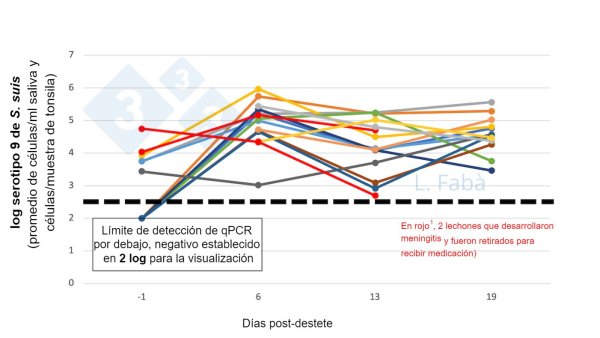

Lluís has worked on and/or published papers and scientific communications for international congresses on various swine topics. His expertise includes knowledge on raw material and feed variability, management and nutrition of the growing and producing sow, PRRSV, Salmonella, E. coli, Lawsonia intracellularis and its relation to the nutritional status of the pig and/or the use of dietary strategies, contamination of raw materials with viruses (e.g. ASFV) and the use of additives and quantitative nutrition and physiology of the sow. In his current position as a researcher, he focuses mainly on piglet nutrition, the relationship between swine diseases and nutrition, and also to a lesser extent on supporting sow nutrition projects at Trouw Nutrition R&D.